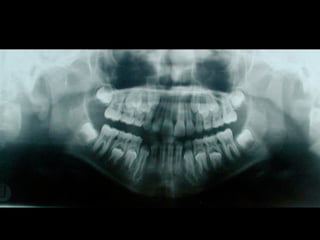

Panoramic (reconstructed from CT)

The most likely diagnosis for the facial asymmetry of this young girl is an

undiagnosed condylar fracture that most likely happen when she falled on a meta

crossbar bar ladder 2 or 3 years ago while she was 4 - 5 years old or so. The

condylar stump has healed and a new condylar head has formed, but the losted

substance of the condyle is gone. Therfore, the height of the ramus has

shortened.

The left ramus and condylar neck are shorter and the left eminence has no slope

if any. Healing and normal growth had reshaped both condyle and eminence.